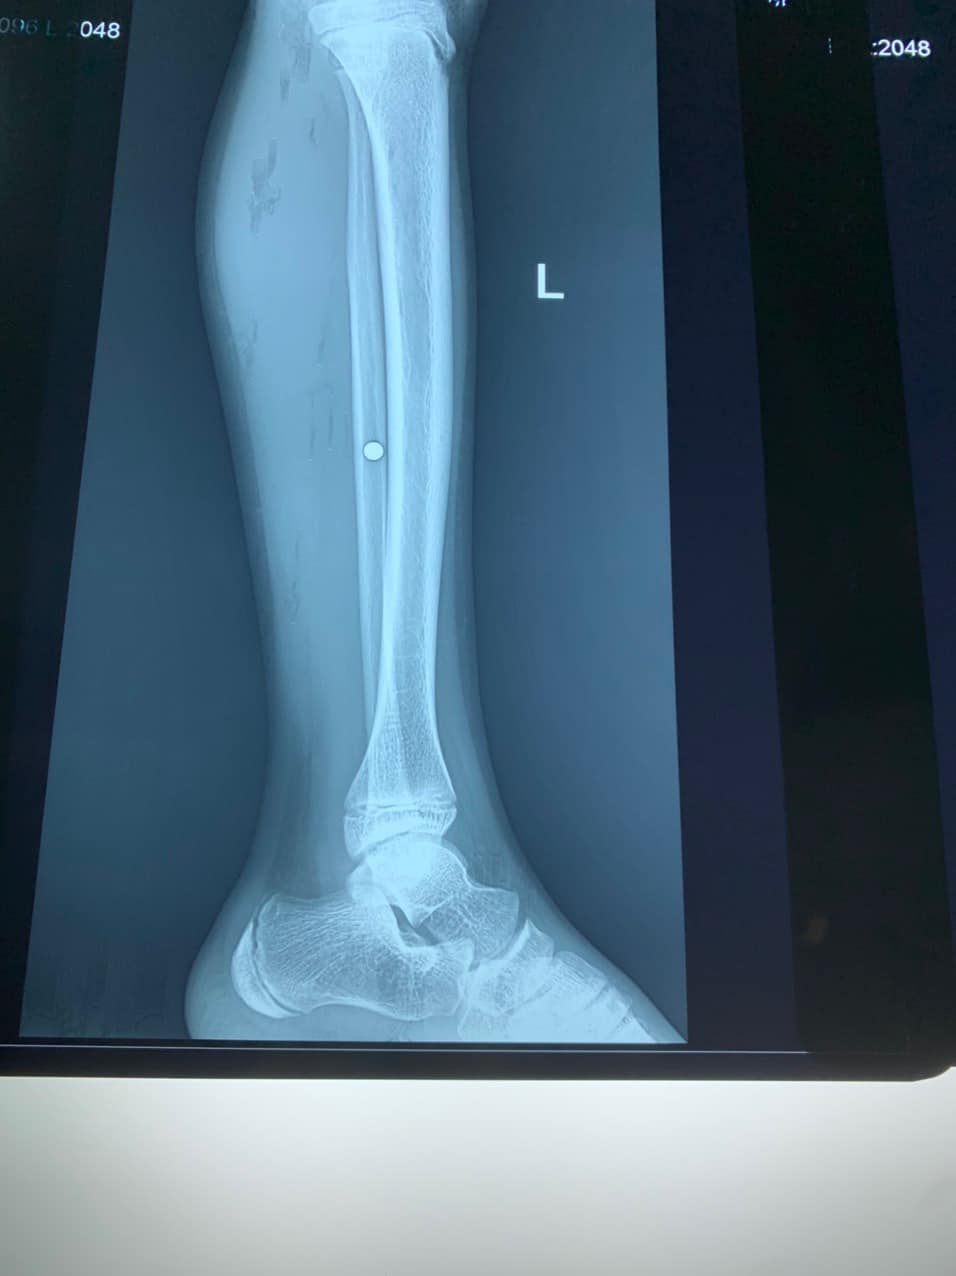

Ngay sau khi tiếp nhận, các bác sĩ thăm khám và làm các chỉ định cận lâm sàng. Kết quả chụp X-quang cho thấy, cẳng chân trái của bệnh nhân bị găm 1 dị vật có kích thước 0,3 cm, cơ cẳng chân trái bị dập nát từ vết thương do hỏa khí gây nên.

Phim X-quang cho thấy viên đạn nằm ở cẳng chân bệnh nhi. Ảnh: BVCC